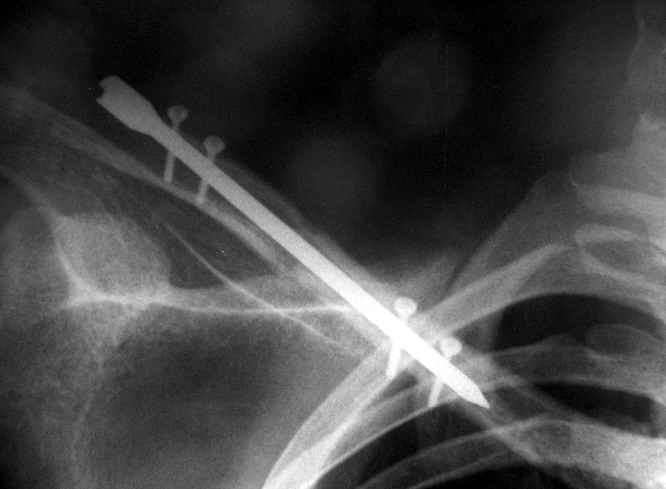

Существует, например, XS nail - фото в приложении, который запирается спицами 2 мм - не знаю, использовали ли его для ключицы, но почему бы и нет.

Один из вариантов, что удалось быстро найти, позже еще найду, но схема примерно такая (первое

вложение).

Мужик кочегар, срок нетрудоспособности 7 недель. Наружную конструкцию сняли через 3 недели. Далее без иммобилизации. Погруженную спицу можно убрать и через несколько месяцев, если жить не мешает.

Раньше не погружали, на рентгенограммах и натуре видно (последние 2 вложения). Как вариант спицы в периферическом отломке могут крепится на трехдырочную приставку, что дает возможность компрессии.